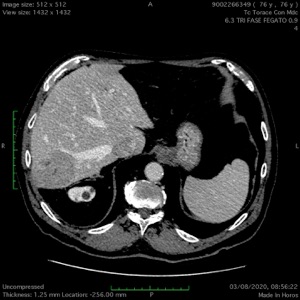

HCC 7 SEGMENTO RECIDIVO: ABLAZIONE MEDIANTE MICROONDE CONGUIDA ECG E CEIOUS

Pz di 77 anni con recidiva locale di HCC in 7s già pluritrattato nella stessa sede con termoablazioni percutanee (5 sessioni). Non resecabile in quanto la recidiva voluminosa (50mm) prende contatto con la sovraepatica dx: il pz non ha i criteri adeguati per una epatectomia dx